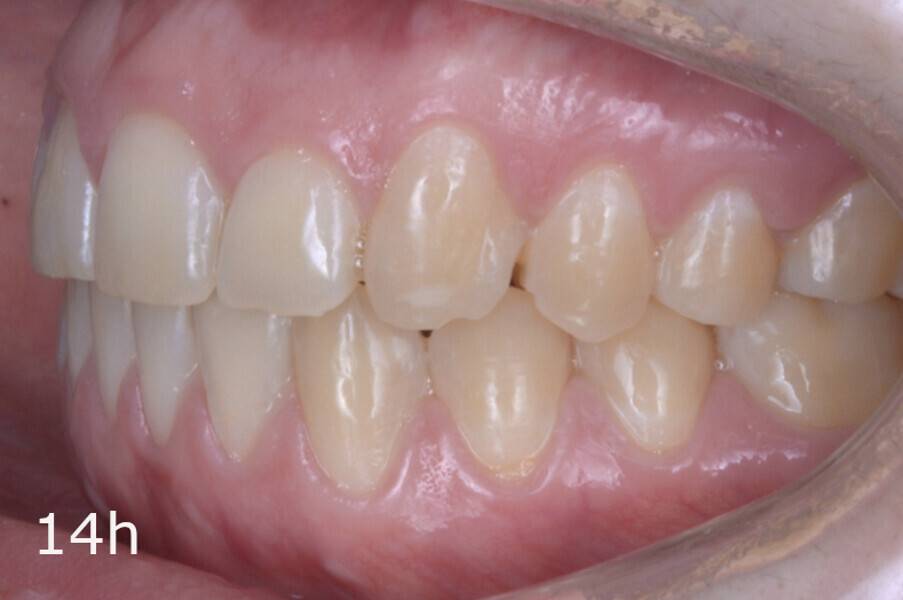

The total treatment time was 15 months. An Angle Class I relationship was established along with adequate anterior and canine guidance, establishing a functional occlusion. This not only ensures optimal masticatory function but also protects the teeth and the temporomandibular joint from excessive force. Maxillary and mandibular fixed retention were installed at the end of the treatment (Figs. 13–19).